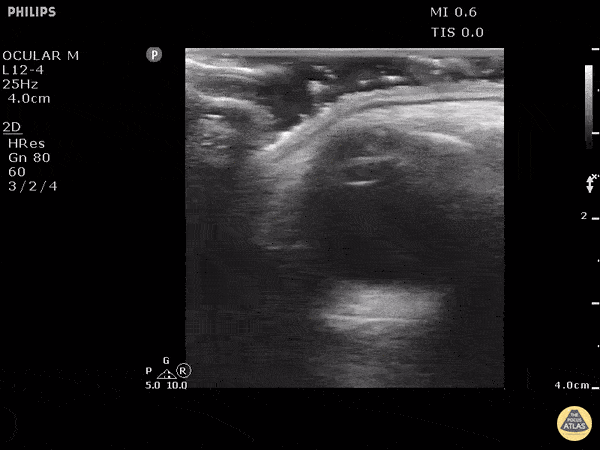

Orbital - Metallic Foreign Body In Orbital Soft Tissue

This is a clip from a patient presenting with foreign body sensation. They had a piece of metal hit their eye a week ago. Previously seen for complaint but told no foreign body seen on exam. On ultrasound clip a hyperechoic structure can be seen adjacent to the globe. Note that with dynamic eye movements the foreign body does not move suggesting this is outside of the globe. Image courtesy of Robert Jones DO, FACEP @RJonesSonoEM Director, Emergency Ultrasound; MetroHealth Medical Center; Professor, Case Western Reserve Medical School, Cleveland, OH View his original post here